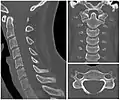

Cervical degenerative changes arise from conditions such as spondylosis, stenosis of intervertebral discs, and the formation of osteophytes. The changes are seen on radiographs, which are used in a grading system from 0–4 ranging from no changes (0) to early with minimal development of osteophytes (1) to mild with definite osteophytes (2) to moderate with additional disc space stenosis or narrowing (3) to the stage of many large osteophytes, severe narrowing of the disc space, and more severe vertebral end plate sclerosis (4).[5][6][7]

X-ray of cervical vertebrae

X-ray of cervical spine in flexion and extension